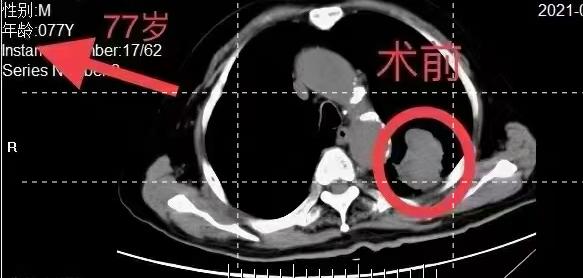

病例分享:77岁高龄老人,肺癌晚期。

粒子植入手术四十天后,看嗲嗲如何逆袭消瘤!

(肿瘤大小约5X4Ⅹ5Cm,粒子术后验证剂量为100Gy)